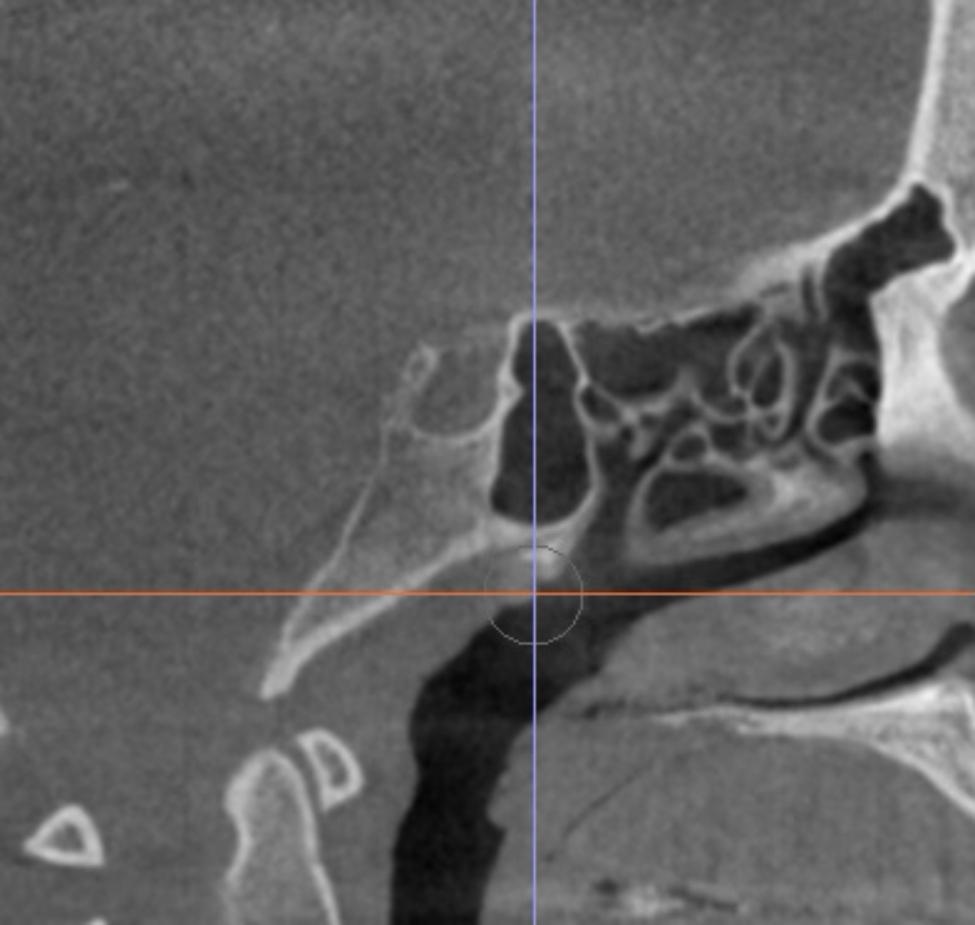

A total of 52 cone beam computed tomographic (CBCT) images were selected with an age range of 18-30 years. Group I comprised 26 patients previously diagnosed with transverse maxillary deficiency, while group II comprised 26 patients with normal transverse skeletal relationships. The length, depth and diameter of the ST were measured by two observers, the shape was evaluated as round, oval or flat and sellar bridging was calculated in each case. An Independent t-test was used to compare between the sellar dimensions in both groups. For assessment of bridging percentage Chi square test was used.

共选择 52 例锥形束 CT(CBCT)图像,年龄范围为 18-30 岁。I 组包括 26 例经诊断为横向上颌骨不足的患者,II 组包括 26 例横向骨骼关系正常的患者。由两位观察者测量鞍区的长度、深度和直径,评估鞍区的形状为圆形、椭圆形或扁平形,并计算每个病例的鞍区桥连情况。使用独立 t 检验比较两组之间的鞍区尺寸。使用卡方检验评估桥连百分比。